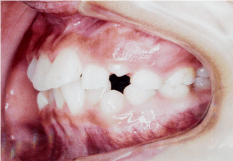

- 開咬(かいこう)

- 噛んでいても前歯がかみ合っていない状態のことで、発音が悪くなったり、前歯でものを噛み切ることが難しくなります。舌の癖や指をしゃぶる癖が原因で起こることがあります。

- 空隙歯列(くうげきしれつ)

- 歯と歯の間に隙間ができている状態で、顎の骨の大きさに対して歯が小さく生えてしまうことが原因です。

隙間があると食べ物が詰まりやすくなり、虫歯や歯周病の原因になります。また隙間から息漏れが生じるのでサ行・タ行・ラ行の発音が悪くなります。